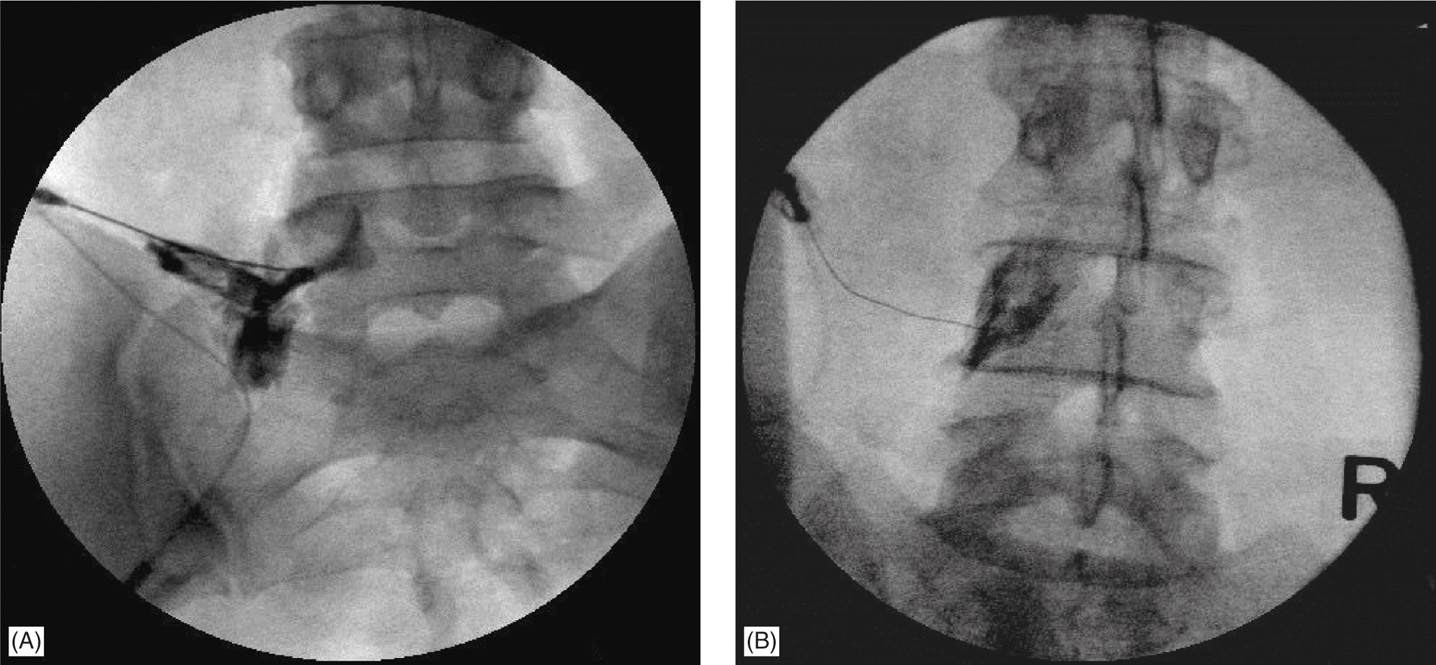

L5S1 interlaminar epidural steroid injection (fluoroscopic guided Lumbar Epidural Steroid Injection L5 S1 Interspace A lumbar epidural steroid injection may be used to reduce the inflammation around the spinal nerves. During the procedure, the patient lies down with. A lumbar epidural steroid injection may be used to reduce the inflammation around the spinal nerves. Epidural steroid injections may help relieve sciatica pain from conditions like degenerated discs. During your lumbar epidural injection, your doctor. Lumbar Epidural Steroid Injection L5 S1 Interspace.

Figure 2 from Comparison of Epidural Steroid Injection between L5S1 Lumbar Epidural Steroid Injection L5 S1 Interspace During your lumbar epidural injection, your doctor injected steroid medicine into the area around your spinal cord to help with pain, tingling, or. During the procedure, the patient lies down with. A lumbar epidural steroid injection may be used to reduce the inflammation around the spinal nerves. A lumbar epidural steroid injection may be used to reduce the inflammation around. Lumbar Epidural Steroid Injection L5 S1 Interspace.

L5S1 interlaminar epidural steroid injection (fluoroscopic guided Lumbar Epidural Steroid Injection L5 S1 Interspace During your lumbar epidural injection, your doctor injected steroid medicine into the area around your spinal cord to help with pain, tingling, or. Epidural steroid injections may help relieve sciatica pain from conditions like degenerated discs. Epidural steroid injections may be classified by their location along your spine — cervical, thoracic or lumbar — and by the path of the. Lumbar Epidural Steroid Injection L5 S1 Interspace.